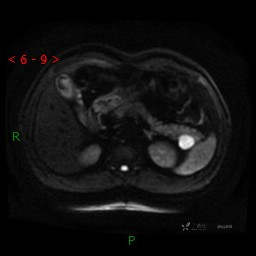

MRI(T1WI+T2WI-fs+DWI+ADC)